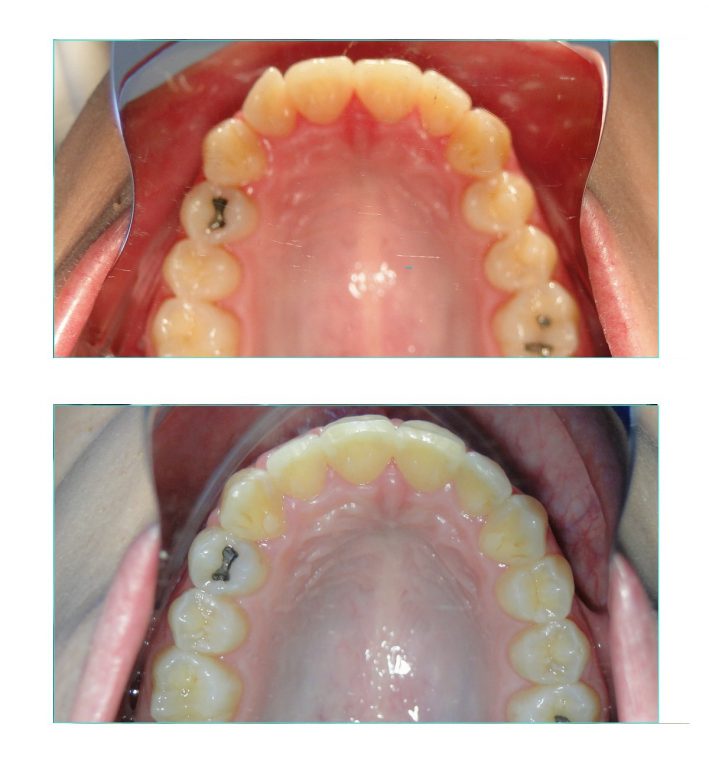

Foi preciso fazer a expansão das arcadas e também o nivelamento e alinhamento dos dentes.

A expansão foi obtida apenas com o uso do aparelho fixo. Não foi usado um disjuntor palatino ou qualquer outro tipo de dispositivo expansor.

Na arcada inferior vemos uma contenção ortodôntica fixa reta. Na arcada superior foi usada uma contenção removível de acetato associada à uma contenção fixa, que foi instalada posteriormente.

Foi sugerido à paciente fazer a correção da gengiva do incisivo lateral superior do lado esquerdo, mas a paciente preferiu deixar assim mesmo,